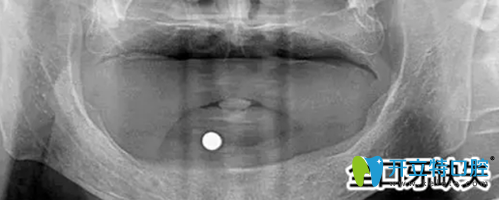

之后萬院長給郭先生做了詳細的檢查,首先給郭先生做了口腔全景片的檢查,發(fā)現(xiàn)郭先生前牙骨量不足,壁薄,需要植骨才能進行種植牙手術(shù)。

郭先生的口腔全景片:

鎮(zhèn)江拜博口腔為郭先生拍攝的口腔全景圖

種植需要避開手術(shù)后的骨缺失區(qū),所以對種植體的承受力和穩(wěn)定性要求較高,同時郭先生對美觀要求較高。萬院長根據(jù)郭先生的需求與口腔情況后為他進行了植骨手術(shù),傷口愈合后,萬院長為他進行CT掃描后確認可以進行種植牙手術(shù)。